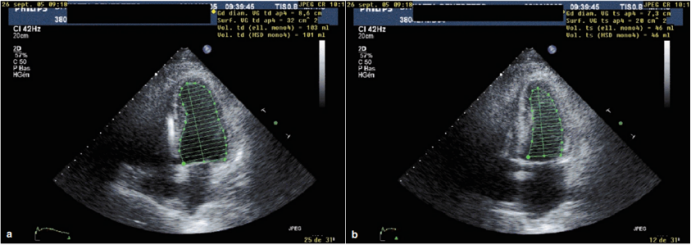

1)短轴缩短率(shortening fraction,SF):SF通过不同维度(直径或面积),反映左室短轴方向的收缩能力。有两种计算方法:①直径法(M超测量):取胸骨旁长轴切面,将M超探头置于乳头肌连接处,确保垂直于室间隔(图13)。计算公式:(舒张末期内径-收缩末期内径)/舒张末期内径。正常范围:24%~36%。②面积法(二维超声测量):取左室短轴切面,探头置于乳头肌连接处并垂直于室间隔,获取舒张末期与收缩末期左室短轴面积(图14)。计算公式:(舒张末期面积-收缩末期面积)/舒张末期面积。正常范围:38%~60%。

图片

13  直径法测量短轴缩短率

14  面积法测量短轴缩短率

2)左室射血分数(LVEF):Simpson法或面积长度法估算左室舒张末容积和收缩末期容积,通过计算公式:(舒张末期容积-收缩末期容积)/舒张末期容积,得到的值即为LVEF(图15)正常值为>60%。

15  超声评估左室射血分数